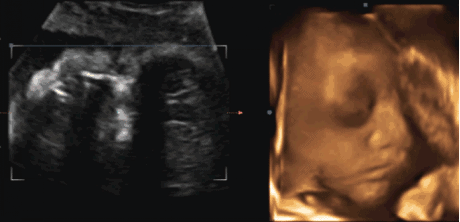

2.四维检查

四维检查属于大排畸检查 , 主要是通过四维彩超来看宫内胎儿情况 , 但是由于胎儿的不配合 , 捂着小脸 , 侧着身 , 导致很多位置看不清楚 , 只能多次检查 。 有网友表示 , 自己四维检查了十多次才合格 。3.糖筛检查